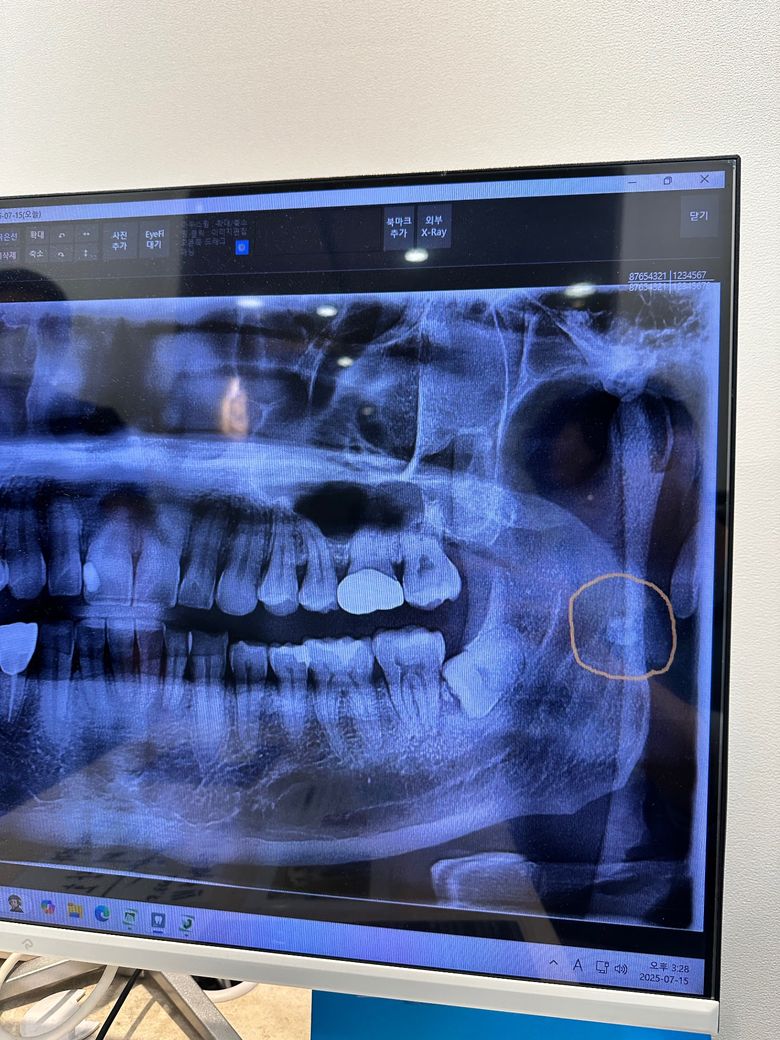

치과 엑스레이 편도결석이라고 하는데

치과에서 편도결석 같다고 이비인후과에 가보라고하는데요 편도결석 맞나요??

크기가큰데 육안으론 안보여서요

홍성의료원